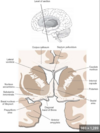

Function of SMA

Motor planning

Consequences of lesions affecting this area

SMA

Paralysis of head and eye movements to the opposite side.

Head turns and looks towards the diseased hemisphere and eyes look in the same direction

Hypokinetic mutism